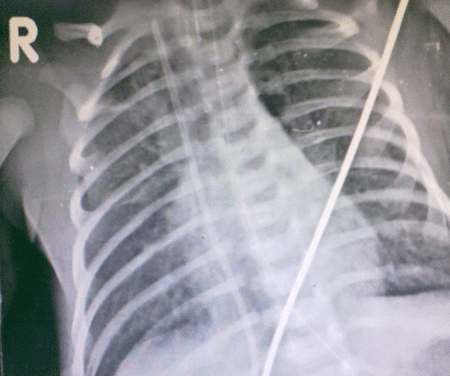

An exploration by a supra umbilical transverse incision was attempted. This was performed in NICU with full relaxation after endotracheal intubation. This decision was to ensure that no time is lost in retrieving the fragment. Despite our efforts we did not find the UVC within the umbilical vein, hence the incision was closed. A repeat skiagram done soon after showed the UVC within the right atrium with the upper end in SVC and lower end in IVC [Fig-2]. Under general anesthesia trans-femoral access was obtained by a 5 Fr sheath. A 15 mm Gooseneck snare was used through a 5 Fr multipurpose A2 catheter. The multipurpose catheter acted as a support preventing the SVC end to slip into the right atrium. The UVC was held just proximal to the tip and snared from the superior vena cava and retrieved. The patient did not have any further complications and was discharged uneventfully as per NICU protocols.

Figure 2: Migrated UVC with upper end supposedly in SVC and lower end in IVC and passing across right atrium. |